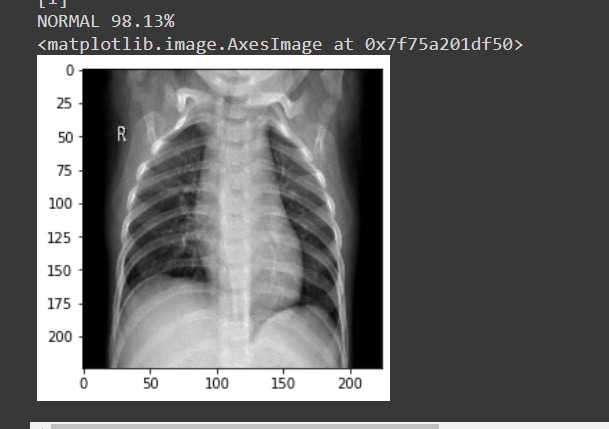

The proposed model has an end-to-end architecture without using any feature extraction methods, and it requires raw chest X-ray images to return the diagnosis. A Flask App is built to which an X-Ray image has to be given as input. It does predict whether the given X-Ray is of a covid infectious person or not.

Built with TensorFlow Keras, Flask. The deep learning model is made with Convolution Neural Networks VGG16 Architecture.VGG16 is loaded with pre-trained weights for imagenet. After defining the model, we need to load the input image with the size expected by the model, in this case, 224×224. The pixel values then need to be scaled appropriately for the VGG model. A flask app is built for user interaction to use the model for prediction of x rays as covid positive or negative